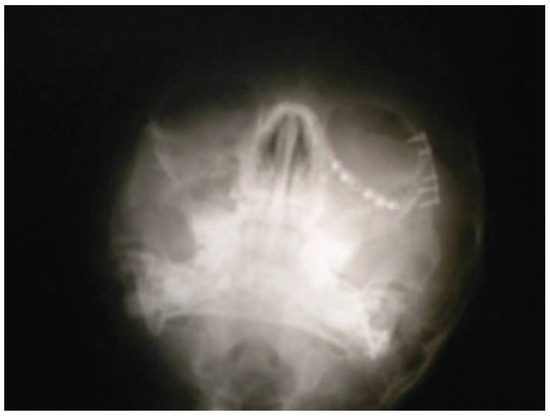

Mandible and Zygomatic Fracture in a 2-Year-Old Patient Due to Dog Bite

Case Report